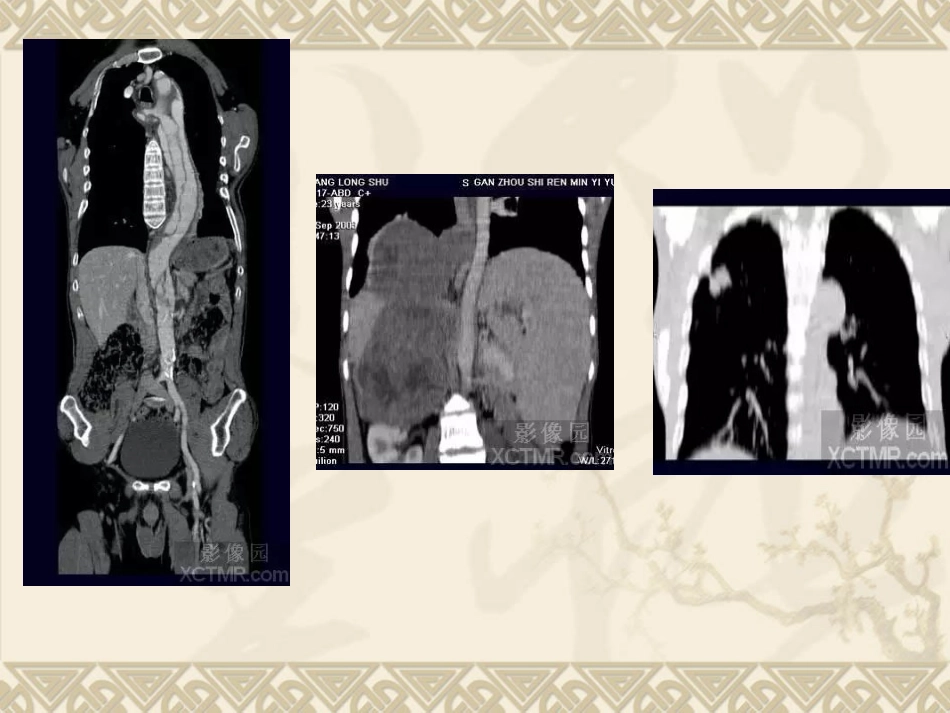

CTA二维及三维影像后处理技术(图文)曲靖市第二人民医院放射科黄江二维图象后处理:①多平面重建(MPR)MPR是从原始的横轴位图象经后处理获得人体组织器官任意的冠状、矢状、横轴、和斜面的二维图象处理方法,与MR图象十分相近,显示全身各个系统器官的形态学改变,尤其在判断颅底、颈部、肺门、纵隔、腹部、盆腔及大血管等解剖和器处理官的病变性质、侵及范围、毗邻关系有着明显优势。②曲面重建(CPR):是MPR的一种特殊方法,适合于人体一些曲面结构器官的显示,如:颌骨、迂曲的血管、支气管等。曲面重建图象的客观性颌准确性和操作者点画线的精确性有很密切的关系。c)计算容积重建(CVR):CVR是MPR的另一种特殊方式。它是通过适当增加冠状、矢状、横轴面和斜面图像的层厚,以求能够较完整地显示与该平面平行走行的组织器官结构的形态,如:血管、支气管等.同时也可以增加图像的信噪比采集数据要求:1)摆正体位;2)头颈部器官和骨骼采集层厚≤1.0mm/每层,胸腹部器官采集层厚≤3.0mm/每层,重叠50%重建;3)重建函数选用FC10(软组织)/FC30(骨骼);4)对手、脚掌骨及关节等部位在确保扫描范围足够的情况下,尽量采用小视野放大扫描;5)胸锁关节、肩关节及髋关节等部位重建图像时须选用RASP以除去伪影干扰。PWh影像园XCTMR.com二维图像后处理技术要点:1)适当调整窗宽、窗位;2)小间隔(<2mm)生成轴位预览图像以确定病变位置和范围;3)针对已确定的病变范围调整间隔、层厚和图像帧数生成MPR图像;4)如病人体位不正,须用斜面重建方式进行调整以获得对称图像。采集数据要求:a)摆正体位:b)采集层厚<2.0mm/每层,重叠重建间隔≤0.5mm;c)选用骨骼重建函数FC30:d)对手、脚掌骨及关节等部位在确保扫描范围足够的情况下,尽量采用小视野放大扫描;e)胸锁关节、肩关节及髋关节等部位重建图像时须选用RASP参数以除去伪影干扰;f)颌面部扫描时病人应取张口位(或咬牙垫)。图像后处理技术要点:a)准确选择预设CT值的上下限,尤其是对较薄的扁骨(如:肩胛骨)重建时应特别慎重以免造成人为的骨质缺损或破坏的假象;b)必要时可用CIipping、Cutting等工具除去扫描托架、固定石膏等影像的干扰和清晰地显露病变:c)对骨关节可用Seed技术施行电子关节分离,以便更清楚地观察关节头和关节盖;d)适当调整伪彩色和遮盖光线的强度,以使图像更清晰、色彩更逼真:e)在判断解剖结构复杂或细小的骨折缝隙和游离碎片时需要借助MPR图像准确定位;f)多角度旋转图豫尽可能清晰、完整地显示病变部位以及与邻近结构的三维空间关系。2)血管系统VR作为MS-CTA的主要后处理技术在血管系统特别是对动脉血管系统病变要以清晰、确切地显示大范围复杂血管的完整形态、走行和病变,图像立体感强,能以多角度直观地显示病变与血管、血管之间以及血管与周围其它器官之间的三维空间解剖关系,其诊断价值已经被临床医生认可。对大动脉血管病变如:动脉瘤、动静脉畸形、狭窄、梗塞、闭塞、夹层和血管壁的钙化等的诊断已经基本取代了DSA检查。对脑动脉瘤的诊断国、内外有关研究报告证实3D-CTA具有很高的准确性、敏感性和特异性,可以确切地检出瘤体直径<3mm的脑动脉瘤。作为一种快速和非创伤性检查手段,可以准确地显示瘤体的位置、形态和大小,评价瘤颈部与瘤体、载瘤动脉和周围血管之间的空间关系,模拟手术入路为选择适当的手术治疗方案提供直观、可靠的依据,可以作为脑动脉瘤的首选影像学诊断方法。近年来,有许多文献报道主张用3D-CTA取代或部分取代DSA诊断脑动脉瘤。脑动脉CTA数据采集要求:a)采集层厚≤3.0mm/每层;b)重叠重建间隔≤2.0mm;c)选用软组织重建函数,如FC=10/43;d)对比剂用量1.0-2.0ml/kg;e)注射速率2.5-3.0ml/sec;f)延迟时间15-20sec.,必要时可用对比剂跟踪技术(Sure-Start);g)扫描方向自下而上;h)对Willis环动脉瘤扫描范围自第一颈椎向上10cm,并尽量采用放大扫描技术。其图像后处理技术要点:a)准确选择预设CT值的上下限,过高或过底均会影像病变显示的清晰度...